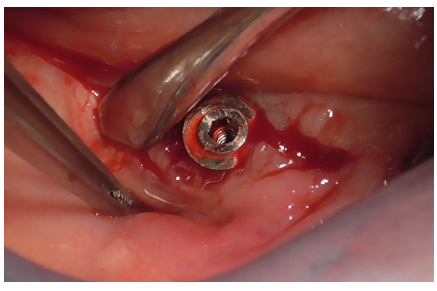

Implant decontamination commenced with an ultrasonic tip (Figure 17) and continued with the diamond ball insert (ES015T) of the Ultrasonic Device (Figure 18).

Figure 17

Figure 18